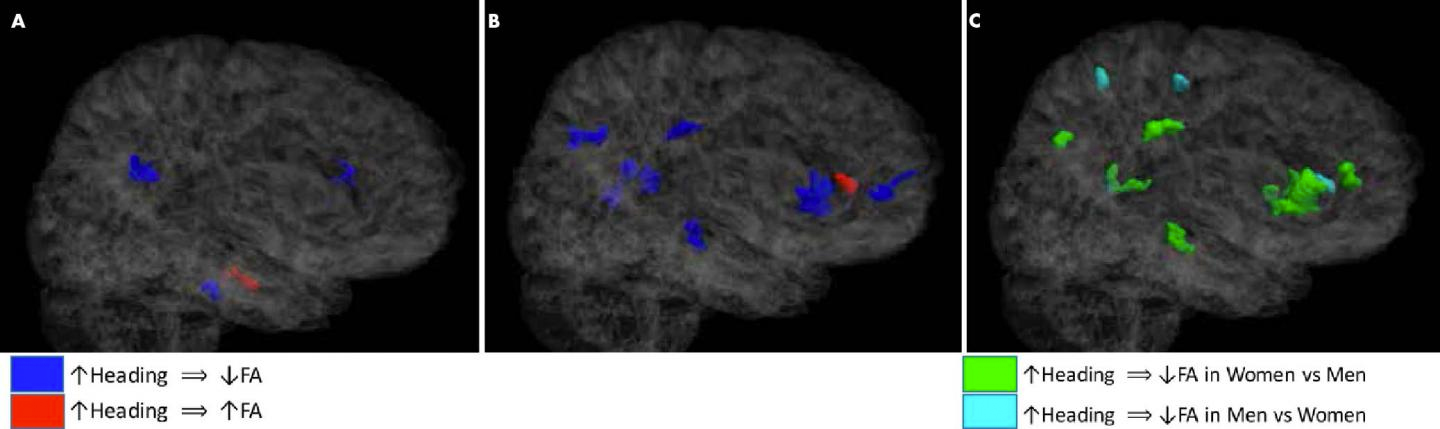

С помощью диффузионно-тензорной визуализации — продвинутой техники МРТ — ученые исследовали микроскопические изменения в белом веществе мозга у 98 футболистов-любителей, 49 мужчин и 49 женщин. Возраст участников составил в среднем 25,8 лет. Все они много лет играли в футбол и отбивали мячи головой. В среднем количество таких эпизодов исследователи оценили в 487 в год для мужчин и 469 в год для женщин.

Диффузионно-тензорная визуализация позволяет получить информацию о фракционной анизотропии — величине, характеризующей организацию структуры мозга. Она зависит от количества и направления проводящих путей белого вещества, по которым движутся молекулы воды. Движение молекул в одном направлении свидетельствует о целостности белого вещества, хаотичное движение — о его повреждении. При хаотичном движении значение фракционной анизотропии снижается.

«Снижение фракционной анизотропии является показателем микроскопических изменений структуры белого вещества, которые могут указывать на воспаление или потерю нейронов»,

— поясняет доктор Майкл Липтон, ведущий автор исследования.

Результаты исследования показали, что фракционная анизотропия была понижена у всех участников исследования в связи с регулярными ударами по голове. Однако у женщин в мозге оказалось намного больше повреждений.

«В обеих группах отрицательное влияние ударов по голове проявлялось в соответствии с количеством ударов, — отмечает Липтон. — Однако у женщин было в пять раз больше микроструктурных повреждений мозга по сравнению с мужчинами, хотя количество ударов было сопоставимым».